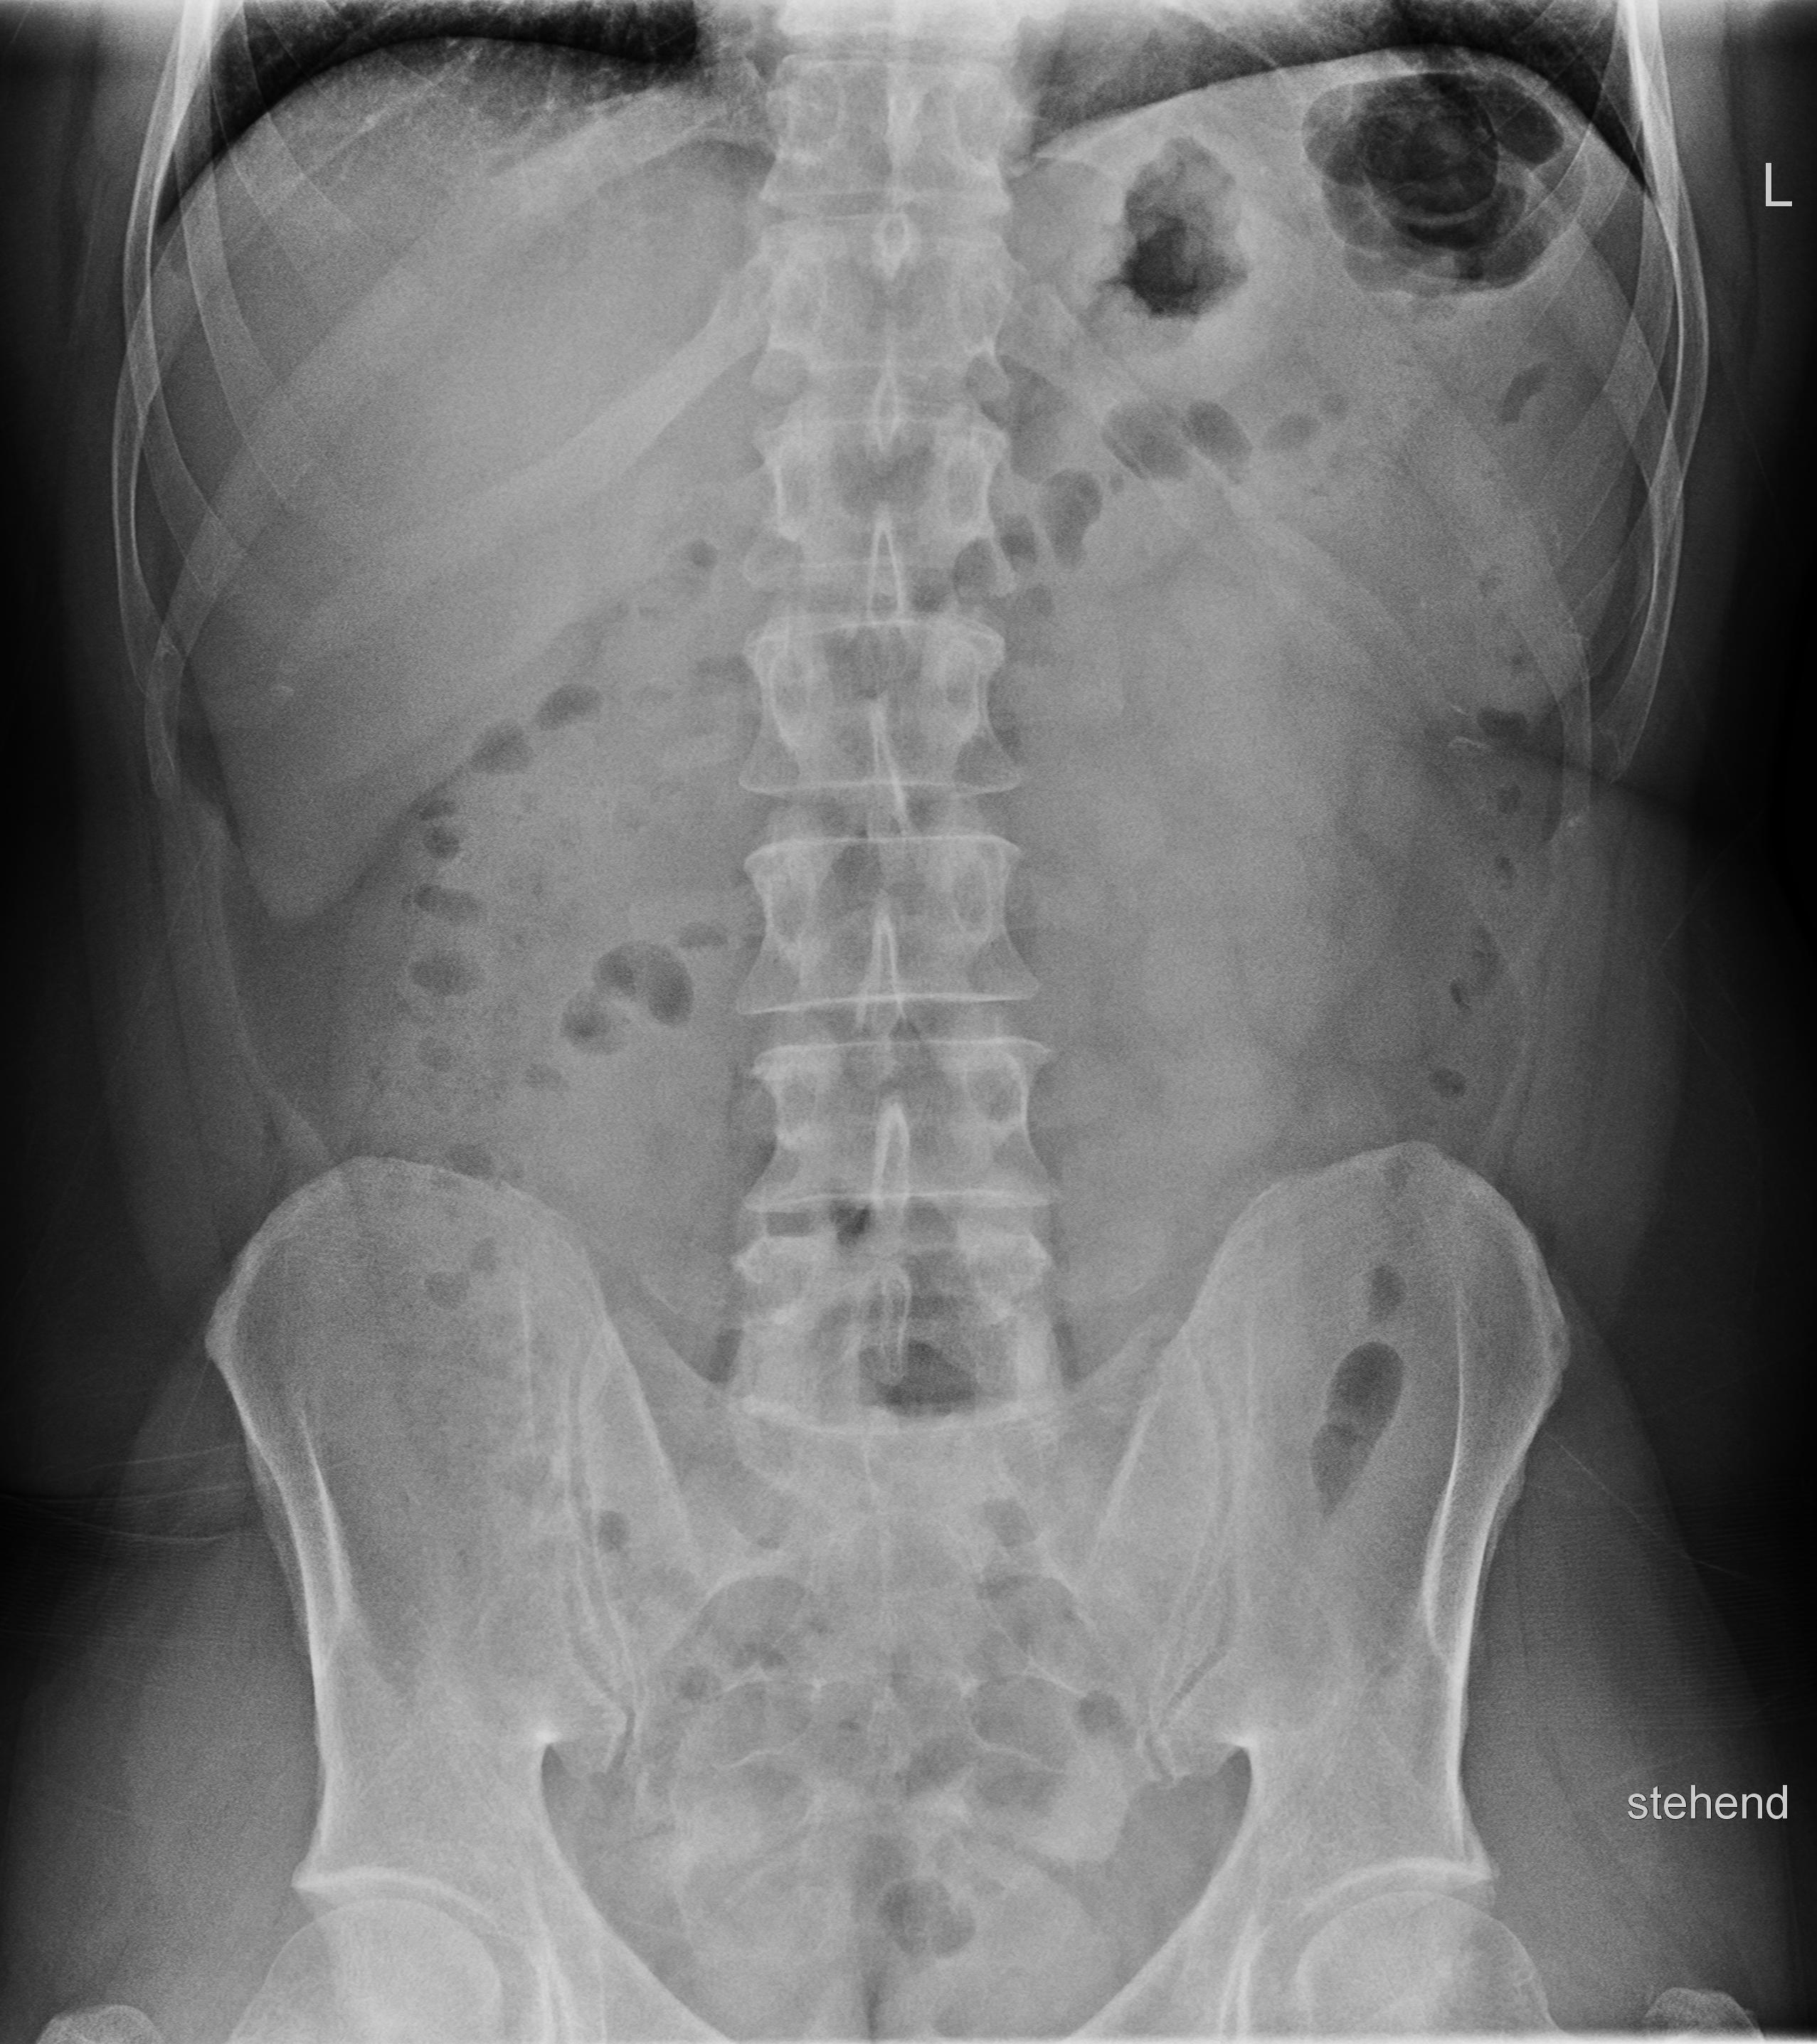

Abdomen im Stehen

Akutes Abdomen, Ileus, Fremdkörper, Konkremente (Gallen-, Nierensteine), Kontrolle von Fremdmaterialen (Magen-, Duodenal-, Dünndarmsonden, ventrikuloperitonealer Shunt...)

• Freie Luftsicheln unter den Zwerchfellschenkel? → perforiertes Magenulcus, Dickdarmperforation (ischämisch, tumorbedingt, entzündlich, Divertikulitis), perforierte Appendicitis, postoperativ? DD Chilaiditi-Syndrom: Coloninterposition zwischen Leber und Zwerchfell – Haustrierung?

• Luft-Flüssigkeitsspiegel? Zentral gelegene Dünndarmspiegel, Arkardenbildung, Distension der Dünndarmschlingen > 3 cm → V.a. Dünndarmileus (zusätzlich) Spiegel entlang des Colonrahmens → V.a. Dickdarmileus Spiegel in Dünn- und Dickdarm, keine ausgeprägte Distension → V.a. Paralyse

• Darmgasverteilung?

Cave: Beim Erwachsenen finden sich normalerweise keine größeren Luftmengen im Dünndarm, wohingegen dies bei Säuglingen/Kleinkindern physiologisch ist. Luft im Dünndarm → Gastroenteritis, Ileus, Peritonitis?

• Psoasschatten? Fehlende Abgrenzbarkeit des Psoasschattens → V.a. retroperitoneale Tumorausbreitung, Abszess, Einblutung auffällig scharfe Abgrenzbarkeit bei Pneumoretroperitoneum → perforiertes Duodenalulcus, Duodenalruptur, Infektion mit Gasbildnern

• Luft in Gallenwegen oder Pfortadersystem? Aerobilie: z.B. bei Gallensteinperforation in den Darm, Z.n. Papillotomie, bei biliodigestiver Anastomose, emphysematöse Cholezystitis Portalvenöses Gas bei Darmgangrän.

• Koprostase? Umschriebene Raumforderungen? Diffuse Verdichtungen, wie z.B. bei Aszites?

• Pneumatosis intestinalis? Infektion mit gasbildenden Bakterien, Darmwandgangrän, pseudomembramöse Enterocolitis

• Verkalkungen? Gefäßverkalkungen, Phlebolithen, verkalkte Lymphknoten